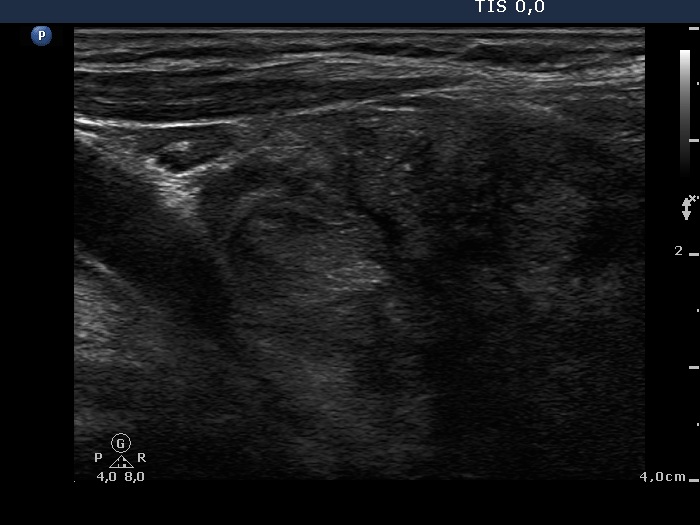

Left lobe, another longitudinal view. Note echogenic foci which may be microcalcifications.